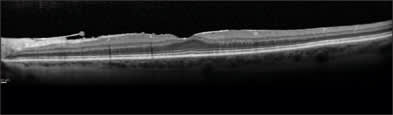

For example, Figure 1 is a 52-year old -4 myope who had a retinal detachment repair recently with buckle.

Figure 1. Despite a retinal detachment repair, this patient did well with a Crystalens IOL. Images courtesy of Steven Safran, M.D.

"The retinal detachment went right up to the edge of the macula and although the macula looks abnormal on exam, the Spectralis shows a rather normal macula architecture in this, his dominant right eye," says Dr. Safran. "This patient did extremely well with Crystalens in this eye, ending up 20/20 and J2 uncorrected.